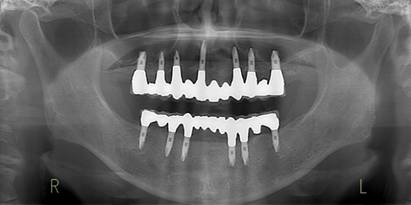

術前パノラマレントゲン写真。根の周りが黒くなり、骨がなくなっていることがわかります

治療後。歯周病で失われた骨が回復しています。使用インプラントはスプラインツイストです。

術前のパノラマレントゲン写真。仮歯を支えている4本の歯は根が残っているだけで抜歯の必要がありました。

63歳術後のパノラマレントゲン。インプラントはスプラインツイスト